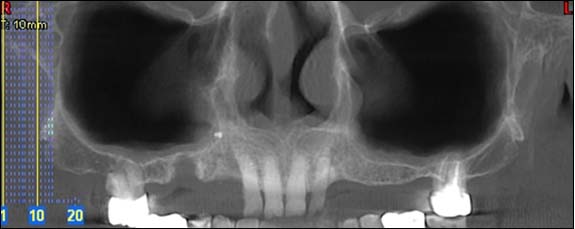

Cette radio permet d'appréhender l'ensemble de votre dentition et des structures adjacentes.

Dernière technologie à notre disposition, cette technique permet de voir en 3 dimensions des images de votre bouche et de mettre en évidence des pathologies ou des anomalies que les autres techniques ne permettent pas d'objectiver.

Reconstruction panoramique